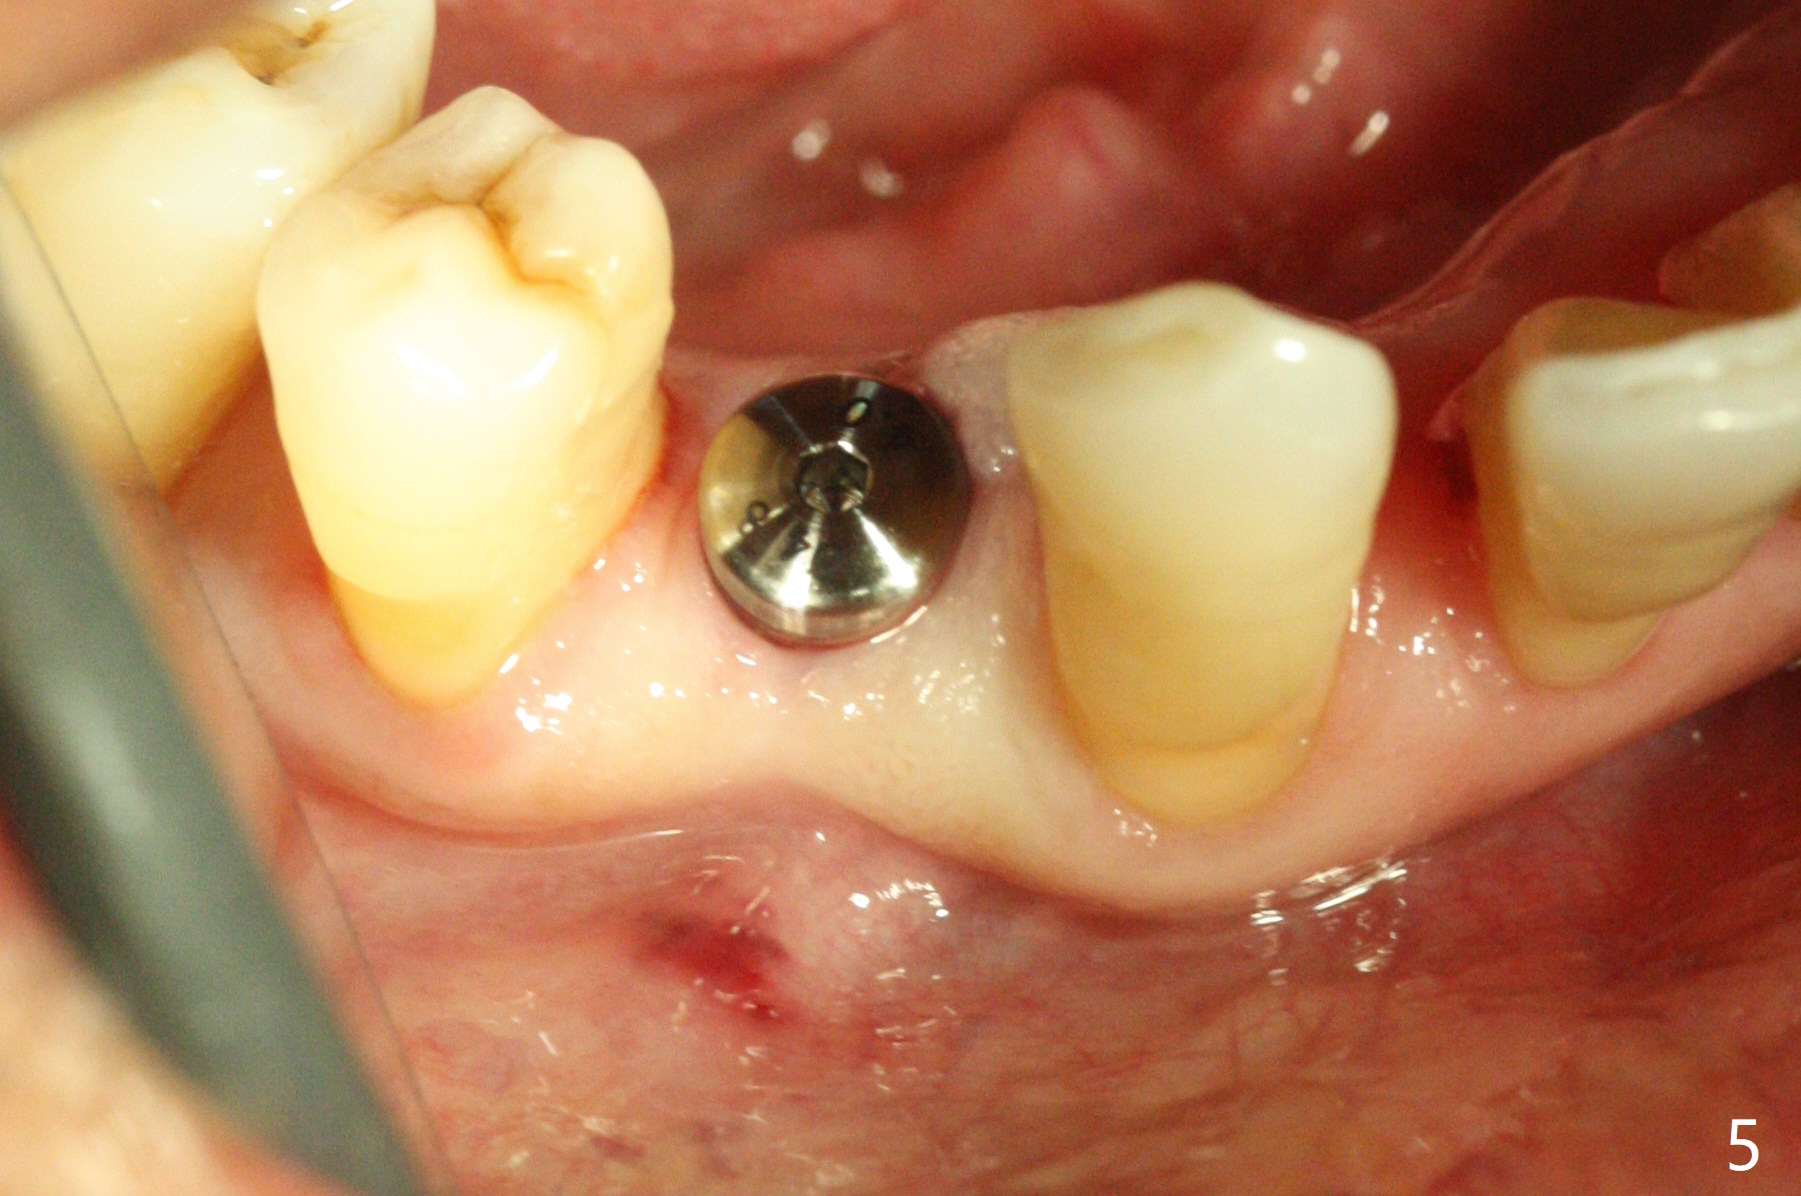

With 9 mm offset, the cylinder portion of the 2.2x8.5 mm drill does not engage to the metal sleeve of the guide at #28 after pointed drill (Fig.1). This issue could be solved with 12 mm offset, although it has no ill effect in this case. Fig.2 shows the site of #28 immediately before bone expansion and after use of 2.2x11.5 mm drill and small-scaled ridge split (^). The bone is so hard that the bone expansion is minimal (Fig.5) with autogenous bone graft and implant placement (Fig.4). There is the bone buccal to the implant clinically. A 5x10 mm implant is placed at #31 in the same appointment (Fig.3). Because of inability to masticate on the left (#18 root fracture with infection), the patient wants to restore #28 and 31 implants 3 months postop (Fig.6,7). The implant at #28 is removed while the healing abutment is being un-torqued without noting bone loss mesially (Fig.7 * (next similar case)). Bone graft is placed (Fig.8 (*),9). Pay attention radiolucency next the apex of the neighboring tooth (Fig.9 ?) before re-placement of an implant. The patient is upset, since he cannot eat. Two weeks later, a 6.5x4(4) mm cemented abutment is placed with 25 Ncm at #31 with a provisional for progressive loading for 2 weeks. Impression is taken. Two weeks later, a permanent crown is cemented without removing the underlying abutment. Two days later, the crown/abutment dislodges; a 6.8x6 mm healing abutment is placed. Eight days, it is difficult to reseat the existing crown and abutment. The mesiodistal edentulous space is limited as well. A 5.2x4(4) mm cemented abutment is able to be seated and torqued (30 Ncm) smoothly; in fact the clearance from the crestal bone (Fig.10 *) is not ample. If the abutment screw becomes loose in function, a profile drill should be used or a 4.5 mm in diameter abutment be placed. The abutment seems to remain in place immediate post cementation (Fig.11). Implant failure is probably due to no socket preservation (buccal plate atrophy) and too early restoration.